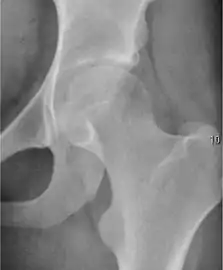

Projectional radiography ("X-ray") is the first imaging technique of choice in hip pain, not only in older people with suspected osteoarthritis but also in young people without any such suspicion. In this case plain radiography allows categorization as normal hip or dysplastic hip, or with impingement signs, pincer, cam, or a combination of both.[1]

Projectional radiography ("X-ray") is currently useful not only in older people in whom osteoarthritis of the hip is suspected but also in younger people without osteoarthritis, who are being evaluated for femoroacetabular impingement (FAI) or hip dysplasia.[1]

Plain radiography allows us to categorize the hip as normal or dysplastic or with impingement signs (pincer, cam, or a combination of both). Besides these, pathologic processes like osteoarthritis, inflammatory diseases, infection, or tumors can also be identified (Figure 1).[1]

Figure 1.

Radiography in normal hip

X-ray in pincer impingement type of hip dysplasia

X-ray of cam

Hip in osteoarthritis

Septic arthritis

X-ray in pediatrics